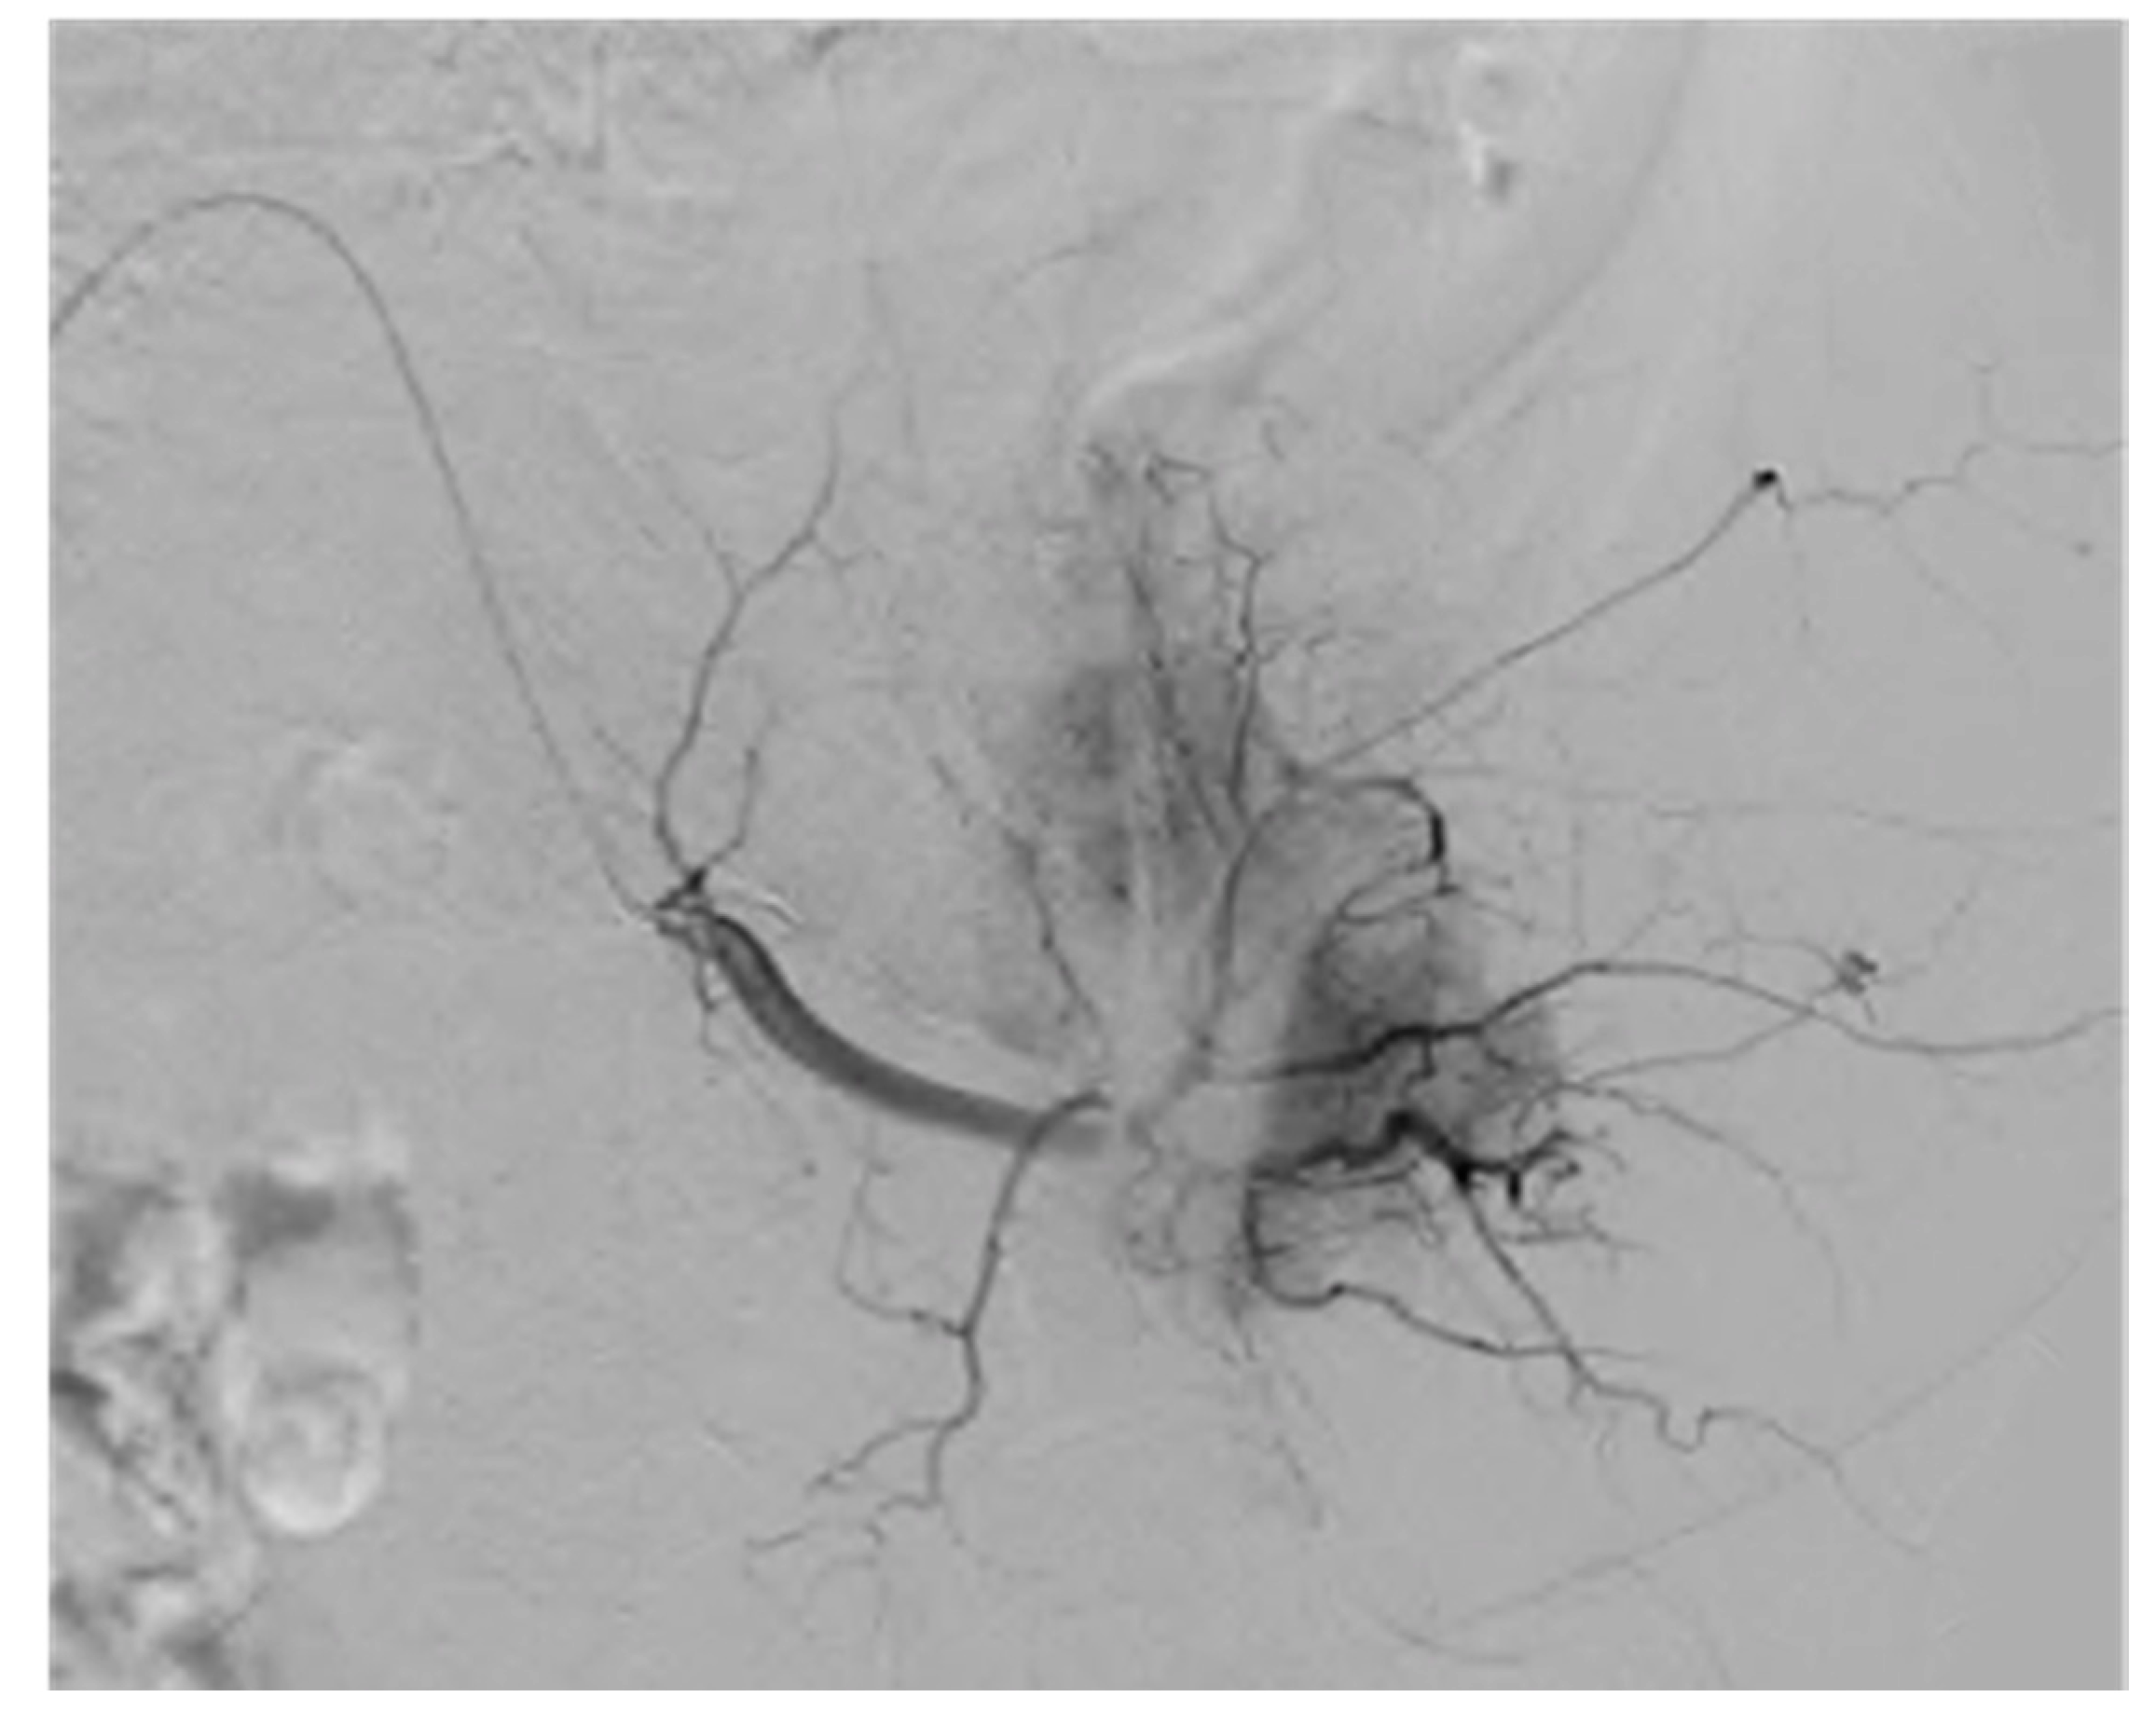

4. Invasive and Non-Invasive Imaging Methods

6.1. Steady-State Imaging